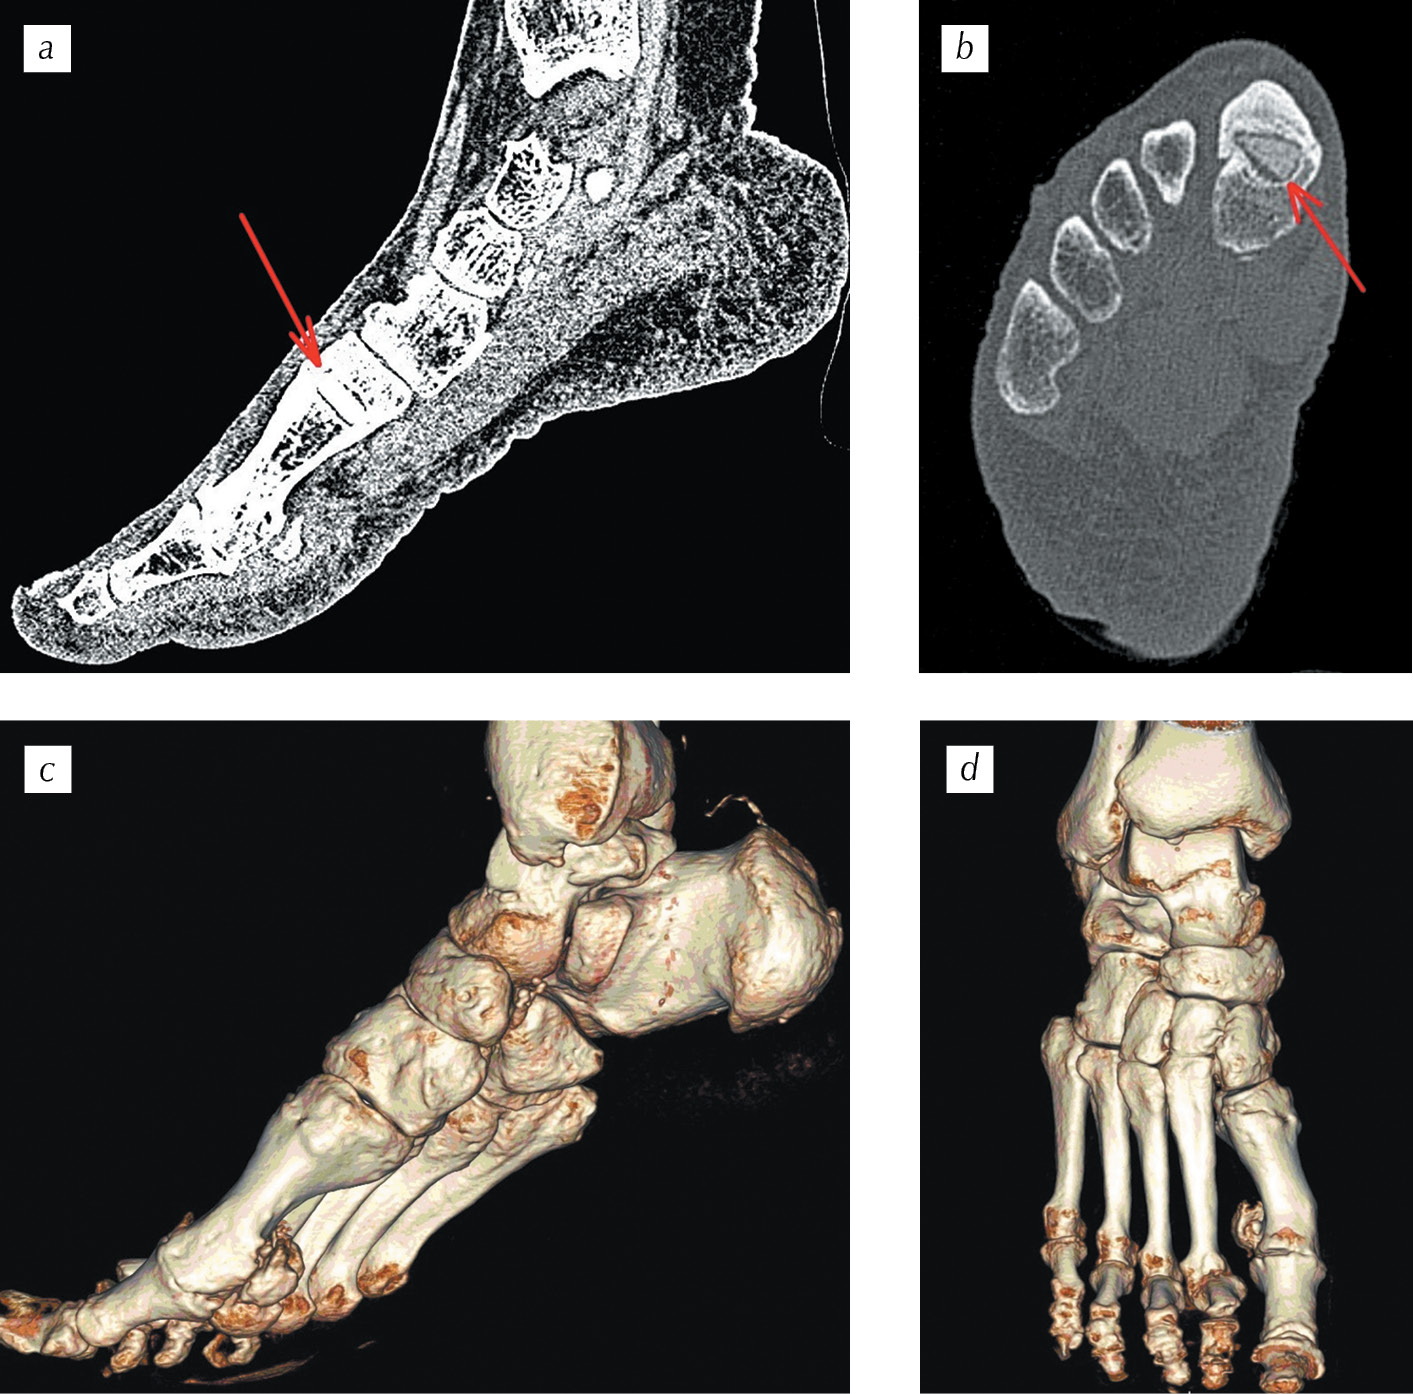

Спустя два года после оперативного лечения функциональные и косметические результаты хорошие, не испытывала дискомфорта при ходьбе и неудобства при ношении обуви (см. рис. 7, 9). Однако при выполнении компьютерной томографии правой стопы в области остеотомии основной фаланги I плюсневой кости прослеживалось наличие углеродного наноструктурного имплантата (рис. 8).

Рис. 8. Компьютерная томография правой стопы пациентки Е. через два года после оперативного лечения: а, b — срезы во фронтальной и в аксиальной плоскостях (стрелками обозначен углеродный наноструктурный имплантат); c, d — 3D-реконструкция костей правой стопы (определяется консолидация места остеотомии I плюсневой кости по типу обрастания имплантата по периферии)

Fig. 8. CT of the right foot of patient E. 2 years after the surgery: а, b — sections in the frontal and axial planes (arrows indicate carbon nanostructured implant), c, d — 3D-reconstruction of the right foot bones (the consolidation of the place of the first metatarsal bone osteotomy is determined by the type of overgrowth of the implant on the periphery)

К сожалению, несмотря на консолидацию места остеотомии I плюсневой кости, которая зафиксирована по типу обрастания имплантата только по периферии (см. рис. 8), интеграции углеродного наноструктурного имплантата с костной тканью не произошло, равно как и не произошло обещанного производителем образования «костно-углеродного блока». Это клиническое наблюдение показывает, что внедренные углеродные наноструктурные имплантаты не всегда обеспечивают активный рост новообразуемой кости в его порах.

Таким образом, по нашим данным и результатам КТ-исследований, интеграции и формирования костно-углеродного блока при применении углеродного наноструктурного имплантата не происходит, консолидация зоны остеотомии идет по типу обрастания имплантата костной тканью по периферии, как инородного тела.